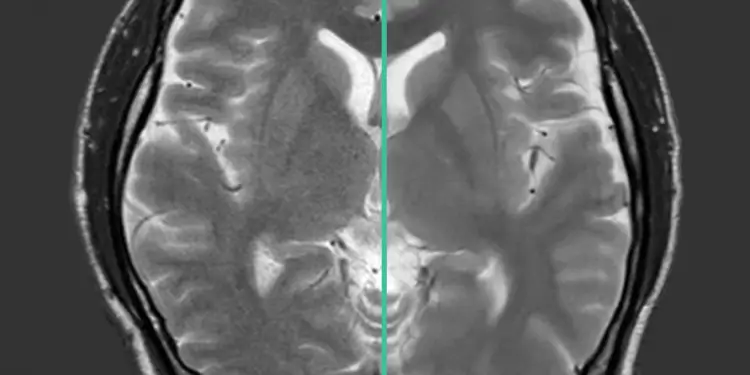

The ”Gibbs” or “truncation” artifact has long been an image quality issue with MRI. Radiologists dealt with it or were compelled to call for longer scan time sequences to address it. Synergy v10 brings DLR Clear, a new AI based algorithm to address the truncation artifact, producing images with mitigated artifact without a scan time extension.